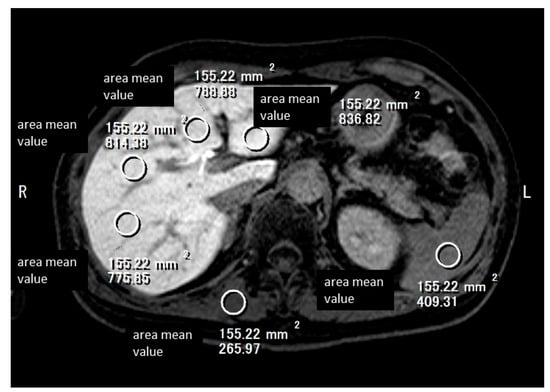

3.4. Extracellular Volume Fraction (ECV)

3.5. Extracellular Volume Fraction (ECV)

- Tago, K.; Tsukada, J.; Sudo, N.; Shibutani, K.; Okada, M.; Abe, H.; Ibukuro, K.; Higaki, T.; Takayama, T. Comparison between CT volumetry and extracellular volume fraction using liver dynamic CT for the predictive ability of liver fibrosis in patients with hepatocellular carcinoma. Eur. Radiol. 2022, 32, 7555–7565. [Google Scholar] [CrossRef] [PubMed]

- Shinagawa, Y.; Sakamoto, K.; Sato, K.; Ito, E.; Urakawa, H.; Yoshimitsu, K. Usefulness of new subtraction algorithm in estimating degree of liver fibrosis by calculating extracellular volume fraction obtained from routine liver CT protocol equilibrium phase data: Preliminary experience. Eur. J. Radiol. 2018, 103, 99–104. [Google Scholar] [CrossRef] [PubMed]

- Mizuno, M.; Tago, K.; Okada, M.; Nakazawa, Y.; Arakane, T.; Yoshikawa, H.; Abe, H.; Matsumoto, N.; Higaki, T.; Okamura, Y.; et al. Extracellular volume by dual energy CT, hepatic reserve capacity scoring, CT. volumetry and Transient-elastographyfor estimating liver fibrosis. Sci. Rep. 2023, 13, 22038. [Google Scholar] [CrossRef]